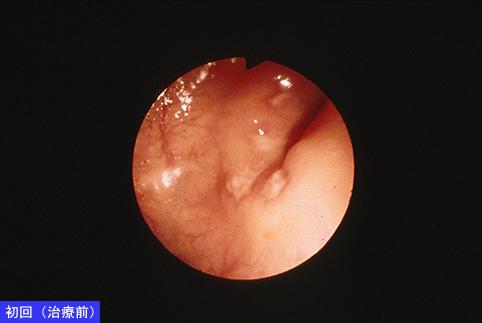

A case of colonic tuberuculosis which was almost completely cured by antituberuculosis medicine.

Inflammatory or ulcerative disease / lesions/tuberculosis

Large intestine(Colon)/Ascending colon

Endoscopy